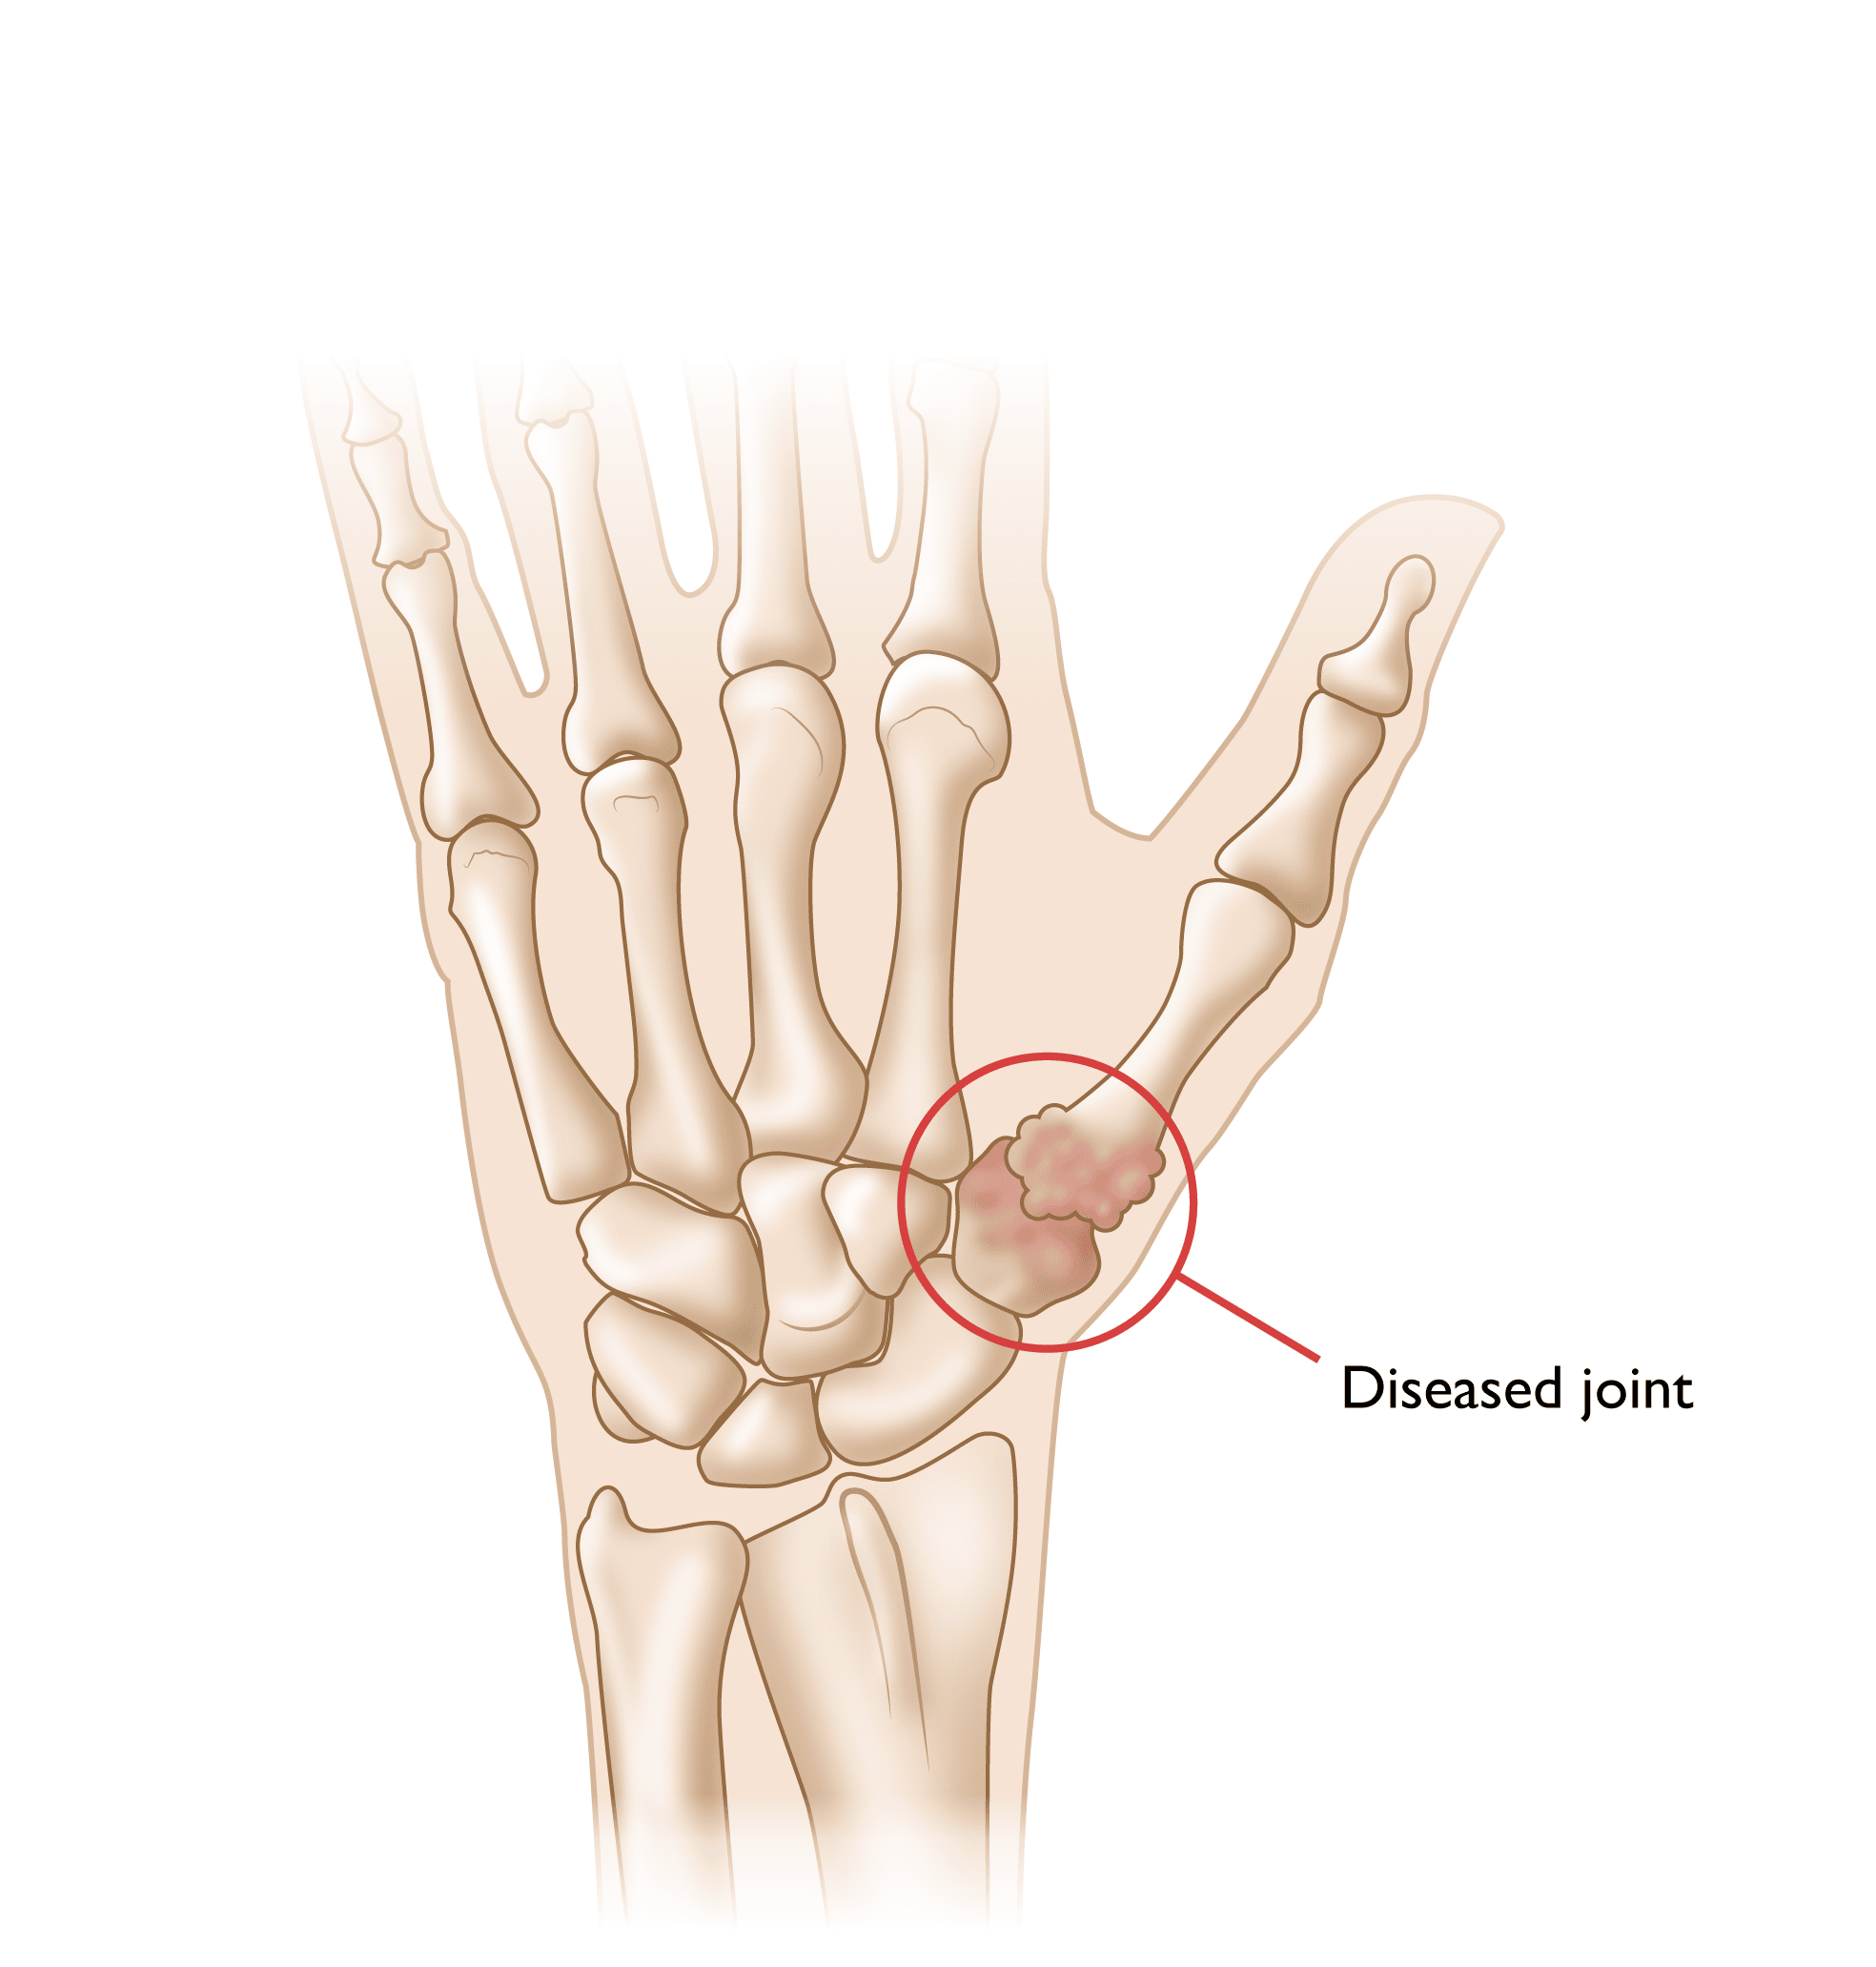

Illustration of arthritis at the base of the thum

Smooth cartilage covers the ends of the bones. It enables the bones to glide easily in the joint. Without it, bones rub against each other, causing friction and damage. Osteoarthritis occurs when the cartilage begins to wear away, typically due to age and use.

The basal joint at the base of the thumb — or thumb CMC joint — is located near the wrist and at the fleshy part of the thumb. It enables the thumb to swivel, pivot, and pinch so that you can grip things in your hand. This joint is highly vulnerable to arthritis as people age.

Arthritis is a condition that affects joints, ultimately resulting in wearing out of the protective cartilage joint surface. In the thumb, the most common site for arthritis to develop is in the basal joint at the base of the thumb — also known as the thumb carpometacarpal (CMC) joint.